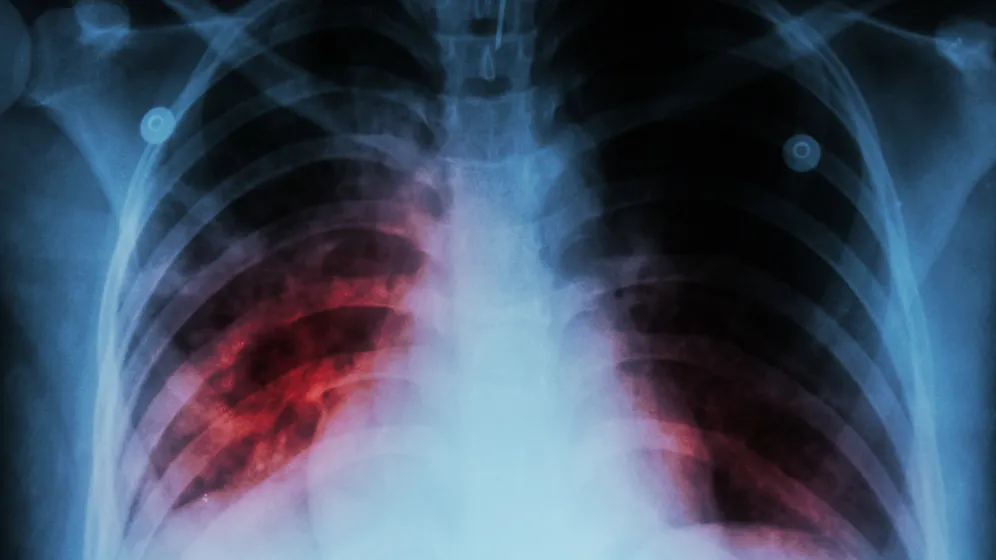

W diagnostyce pojawiają się testy zdolne do szybszego wykrywania oporności na leki, a także narzędzia oparte na sztucznej inteligencji, które analizują obrazy radiologiczne pod kątem wzorców charakterystycznych dla gruźlicy. W połączeniu z programami zdrowia publicznego mogą one skracać czas od wystąpienia objawów do rozpoznania.